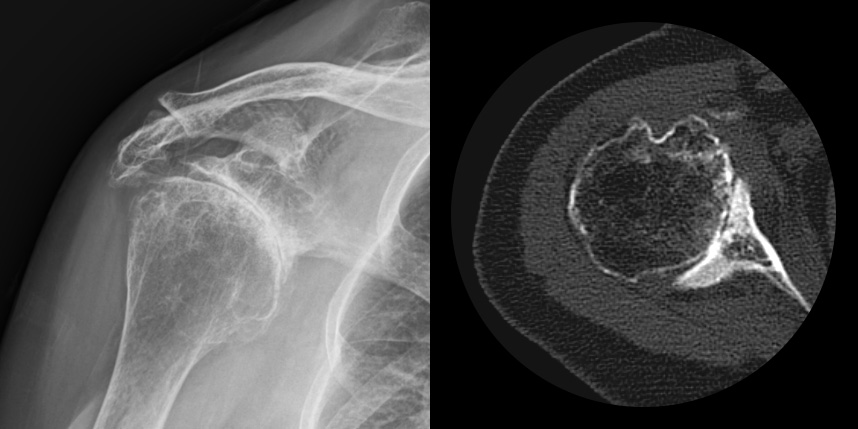

어깨 퇴행성은 많이 써서 닳고 노화에 따른 변화가 생긴 것으로, 말 그대로 어깨가 많이 사용되면서 연골이 닳아서

마모돼어 생기는 관절염입니다. 어깨 회전근개 관절병증 원인으로는 어깨 힘줄 파열을 방치했을 때 관절이 틀어진 상태에서 계속

사용하게 되면 관절이 많이 상해서 관절염까지 진행되며, 이런 경우 회전근개파열의 결과로 생긴 관절병이라고 합니다.

최근에 퇴행성 관절염, 류마티스 관절염 이외에도 많은 환자가 발생하고 있습니다.

초기에는 통증이 미약하나, 시간이 경과하면서

통증이 세집니다.

어깨를 움직일 때마다 모래가 갈리는 것 같은 느낌의

통증이 발생합니다.

어깨 관절 부위가 붓고, 부기가 빠지지 않습니다.

어깨를 들어올리거나 돌리는 운동의 범위가 감소됩니다.